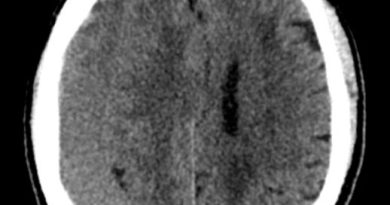

3 yaş K, santral apne, rizomeli

Tanınız nedir?